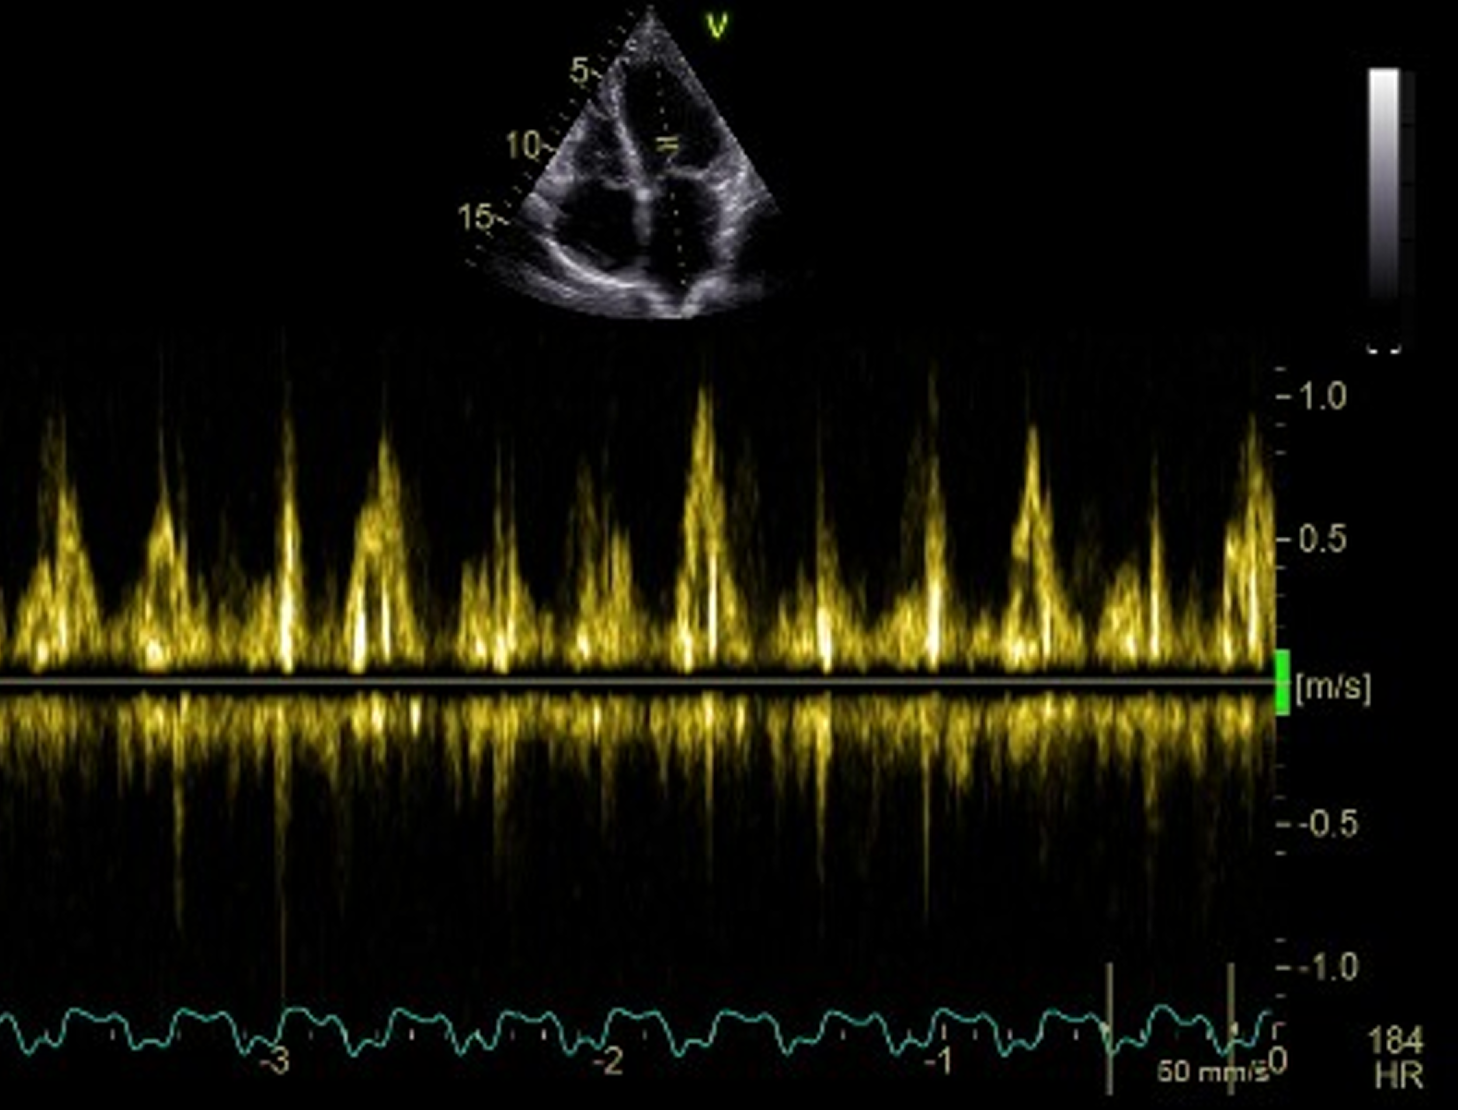

Obr. 3. Zatím definitivní stav: původní stimulační systém DDD zprava, z levé strany CRT-D.